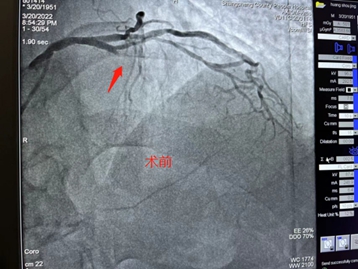

3月20日,是值得纪念的日子,商城县人民医院心血管内科心脏介入团队在郑州大学第一附属医院专家的指导下,顺利完成了6台高难心脏介入手术治疗,打破了我院开展PCI项目以来的单日最大量纪录,在我院心脏介入技术发展过程中具备里程碑式意义。 据心血管内科熊晨晖主任介绍,当日共有7人接受手术,其中6人分别完成了疑难复杂的支架植入和药物球囊治疗,术后血流再通良好,患者及家属对治疗效果均非常满意。 在北京安贞医院马长生教授团队的帮扶下建立的国家标准化心血管疾病中心,驻扎式派出叶益聪教授等专家的带教下及郑大一附院,郑大二附院知名专家的指导下,商城县人民医院心血管内科于稳中求进,不断探索学习,自2018年10月至今,已成功地完成支架植入治疗近600例,造福商城县广大心血管疾病患者。 一台台介入手术的圆满完成,一位位患者因及时救治而重获新生,无不体现着商城县人民医院心脏介入团队日益精进的诊疗技术,也显示出我院在介入治疗领域已具备较强的综合实力。时间就是生命,时间就是心肌,与时间赛跑,与死神搏斗!商城县人民医院心血管内科团队将会不懈努力,不断进取,为广大心血管疾病患者的健康保驾护航! 就医地址: 冠心病监护病房(CCU):2号病房楼4楼。 咨询电话:0376—7975373; 心血管内科病区:2号病房楼4楼。 咨询电话:0376—7973137